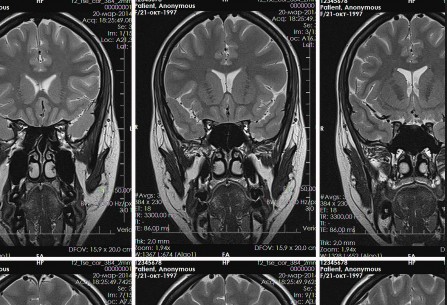

На фотографии головного мозга здорового человека можно увидеть нормальное расположение глазниц, слуховых проходов, зрительных нервов. Примеры изображений МРТ головного мозга позволяют увидеть разницу между нормальным и патологическим состояниями.

Изображения, полученные при прохождении МР-сканирования – это информативные трехмерные фотоснимки, сделанные в нескольких проекциях. Стоит ли делать анализ МРТ головного мозга? Несомненно, да, ибо без интерпретации снимков, выполненных врачом-радиологом, невозможно поставить истинный диагноз и назначить полноценное лечение.